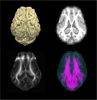

In vivo Adult Yucatan micropig brain template

This is a T2-weighted MRI brain template constructed from 16 adult Yucatan micropigs aged 6 months to 2 years old, created using non-linear registration methods (Advanced Normalization Tools). Tissue probability maps for gray matter, white matter, and CSF are also included. Estimated whole brain tractography from one individual is included as a sample. Please refer to the following article when using this template: Chang SJ, Santamaria AJ, Sanchez FJ, Villamil LM, Pinheiro Saraiva P, Rodriguez J, et al. In vivo Population Averaged Stereotaxic T2w MRI Brain Template for the Adult Yucatan Micropig. Frontiers in neuroanatomy 2020;14(89).